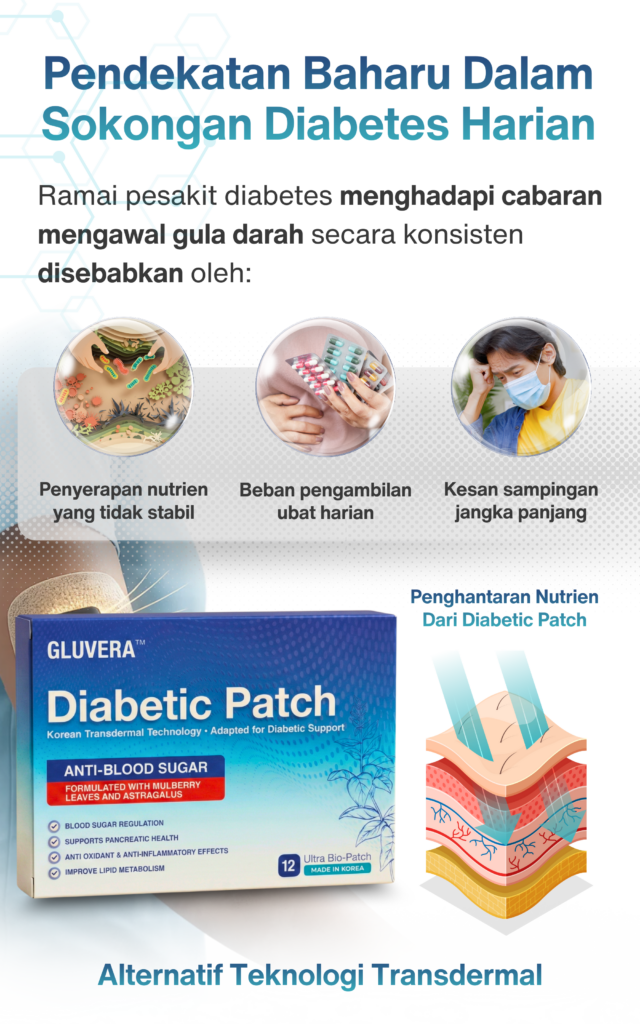

Adakah GLUVERA™ sesuai untuk penggunaan jangka panjang?

Ya. GLUVERA direka sebagai sokongan harian berperingkat, sesuai untuk penggunaan konsisten jangka panjang.

Adakah GLUVERA™ membebankan perut atau buah pinggang?

Tidak. GLUVERA tidak perlu ditelan, membantu mengurangkan beban pada sistem pencernaan dan organ dalaman.